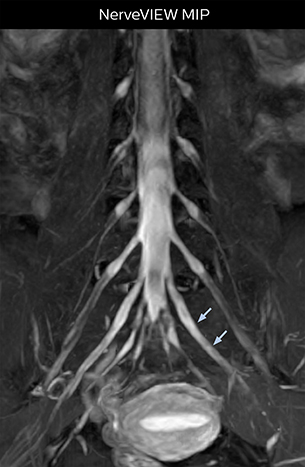

At Northern Fukushima Medical Center in Japan, excellent MRI visualization of nerves helps support confident diagnoses and informs surgical treatment decisions for patients with lower limb symptoms. MRI technologist Tanji and orthopedic surgeon Dr. Yabuki share how direct nerve visualization with the 3D NerveVIEW method adds information when diagnosing atypical herniations. The additional insights changed their way of working and benefit their patient care, as illustrated by some clinical examples.

“In patients with lower extremity neurological symptoms, NerveVIEW helps us to determine the disease matching the patient’s symptoms by directly visualizing the nerves. We use the sequence mainly, when there is suspicion of intraforaminal stenosis, extraforaminal stenosis or lateral disc herniation, which is often based on routine T2- and T1-weighted images. Additionally, the excellent depiction of the course of nerves makes NerveVIEW a good navigator when applying treatment such as block therapy or surgery.”

“In such case, we would then browse through axial T2-weighted MR images slice by slice and mentally reconstruct the actual situation based on both radiculography and MRI. Fortunately, NerveVIEW can now very well show nerve courses and presence of nerve compression or edema in one single image series.” “We have often seen NerveVIEW directly depict details of the nerve compression that were not observed by radiculography. Therefore, we think that with NerveVIEW we can reduce the number of invasive examinations, especially for some patients with lumbar plexus symptoms.”

“Before NerveVIEW, diagnosis by MRI alone was sometimes difficult, unless there was a strong suspicion based on clinical symptoms,” says Shoji Yabuki, MD, DMSc, Orthopedic surgeon at Fukushima Medical University School of Medicine. “This is why we routinely perform selective lumbosacral radiculography (nerve root block) and x-ray in such cases. However, radiculography can only depict nerves as far as the contrast agent reaches. When a nerve is distorted by compression, the contrast agent will not pass through this compressed area, preventing us from evaluating the full nerve compression.”

The key concept in MR neurography, Dr. Yabuki stresses, is the ability to directly visualize spinal nerves, versus inferring the presence of pathology indirectly. “Before NerveVIEW, we estimated compression of the nerve by looking for the presence or absence of fat signal on other MR images,” he says.

“For example, in sagittal images, when the presence of fat is observed in the intervertebral foramen, it suggests that there is a margin around the nerve. Similarly, the absence of fat indicates that the nerve is being compressed. So, we used to deduce nerve compression indirectly. With NerveVIEW, however, we can observe the condition of the nerves directly, regardless of the presence or absence of fat. We always prefer such direct observation of anatomy over having to make an inference about it.”

“Although symptoms of typical disc herniation and atypical hernia are very similar, the actual site of herniation is different. It is therefore important to characterize the nerve’s condition both inside and outside of the intervertebral foramina. “Conversely, if we see no abnormality in NerveVIEW, we can assume at least that there is no severe condition that requires surgery. Like this, it can help us avoid unnecessary surgery. NerveVIEW can have a tremendous impact in this way.”

“NerveVIEW is really useful for those cases where a nerve disorder is strongly suspected based on the clinical examination but our regular MRI images do not show any findings. These atypical herniations and spinal canal stenosis, occurring in 5% to 15% of the total lumbar herniation/stenosis cases are our main target when using NerveVIEW,” says Dr. Yabuki.